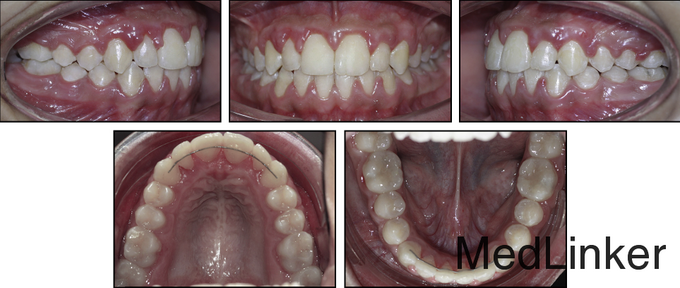

3年后复诊,如图,仍然稳定。快扩和慢扩用于生长发育的患者,还是比较成功的,对于骨龄已经成熟的孩子,外科手术辅助的扩速腭部扩开可能是治疗的选择,本病例中的骨皮质切开术可以作为外科手术的替代方法,诱发颊侧的牵张成骨效应,促进表面骨质的沉积。相比于腭部切开手术,降低了风险。(该病例摘自Am J Orthod Dentofacial Orthop 2015;148:138-53 doi: 10.1016/j.ajodo.2014.08.023.)